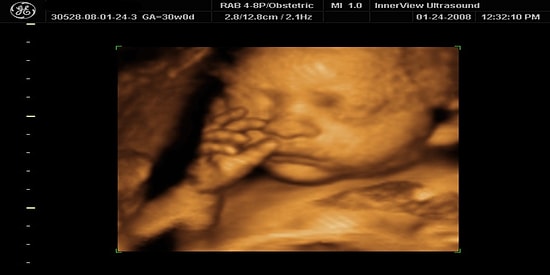

Annelik büyülü olduğu kadar zor da bir iş kuşkusuz, özellikle de ilk kez çocuk sahibi olan bir kadın için... Doğuma kadar süren duygusal, fiziksel ve ruhsal değişiklikler doğumdan sonra da devam eder gider.  BuzzFeed çocuk sahibi kadın okuyucularından ilk kez anne olanlara tavsiyeler vermelerini istemiş, biz de en iyi seçilen maddeleri sizler için derledik.